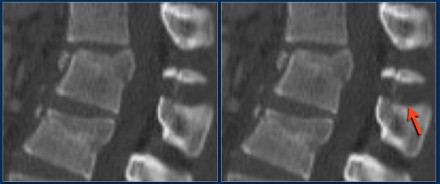

The findings are:

- The main feature is posterior distraction with horizontal fractures of posterior elements (red arrow)

- Avulsion of a spinous process (yellow arrow)

- Widening of facet joint (green arrow)

- Burst-type fracture

In this case some would call this a burst fracture with PLC-injury i.e. 2+3 points.

However the distraction is the most important finding, i.e. distraction and PLC injury, i.e. 4+3 points.